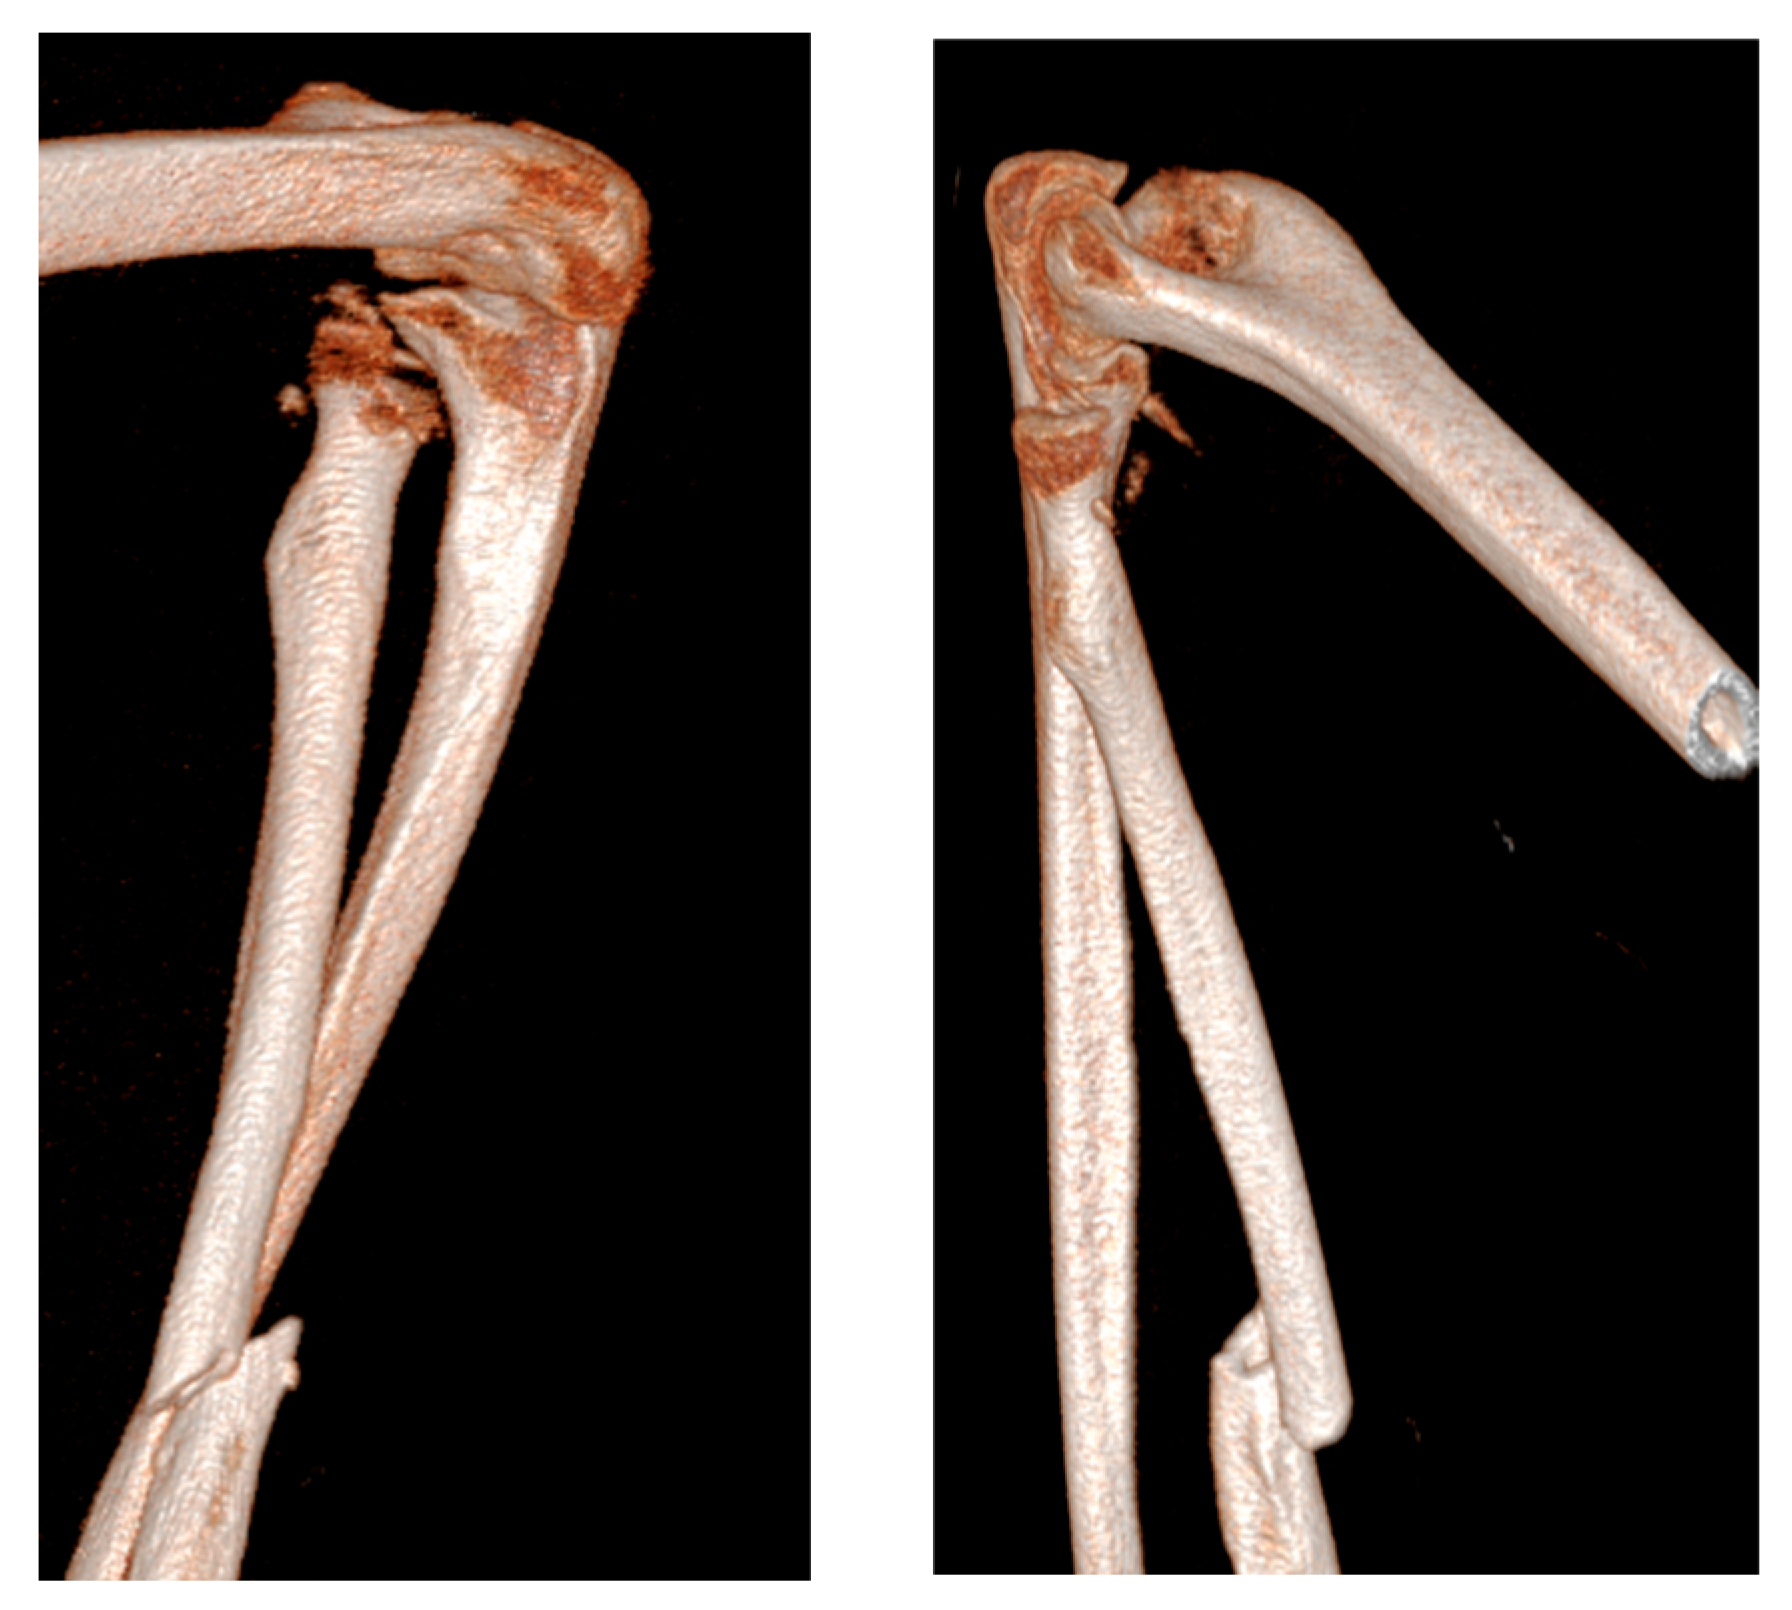

Postoperatively, the arm was immobilized in a neutral-flexed position using a BAM-type plaster splint for 15 days. Following immobilization, the patient began a regimen of protected active and passive mobilization to restore range of motion. A targeted physiotherapy protocol was initiated one month after surgery to support the recovery of elbow and forearm function. At the two-year follow-up, the patient had achieved full recovery of elbow flexion and extension. However, some limitations in forearm pronation and supination persisted, likely due to her pre-existing condition, which was further investigated with a repeated X-ray (Figure 4). The timeline of findings, procedures, and outcomes is summarized in Table 1.

Figure 4. Two-year follow-up X-rays.